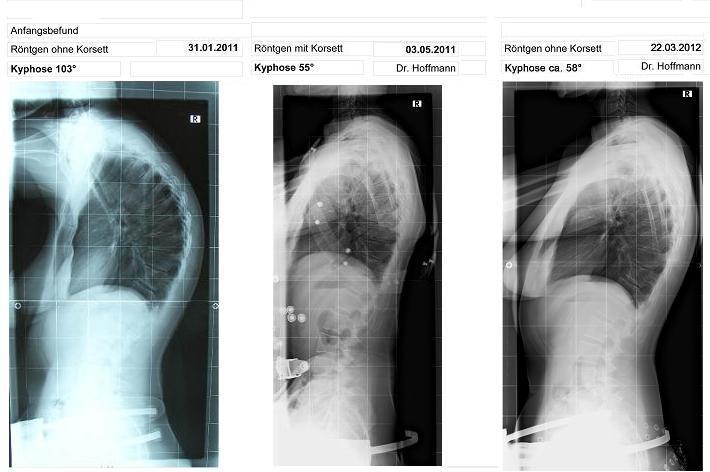

ich denke, die Gradzahlen sind ungefähr gleich geblieben. Die drei Grad liegen ja auch in der Messtoleranz, ich habe mir auch gerade überlegt, ob das mittlere Bild nicht mit dem rechten identisch ist, aber sowas lässt sich auch noch schnell korrigieren, wenn es wirklich die gleichen Bilder sind. Aber wenn man von den Ausgangswerten ausgeht, ist das schon eine beachtliche Leistung, eine Hyperkyphose von 103° auf 55°, bzw. 58° runter zu korrigieren. Daran sieht man, dass die WS trotz Erwachsenenalter noch beweglich ist. Solche Ergebnisse sollten so schnell wie möglich veröffentlicht werden, damit auch die Fachleute davon überzeugt werden, dass ein korsett bei Erwachsenen was bringt.

01/11 R. o. Korsett-103°

05/11 R. m. Korsett-55°

03/12 R. o. Korsett-58°

Ich dussel hab Sloopy die falsche Datei geschickt. Wie Kaffeetrinker schon festgestellt hat, waren das mittlere und rechte Bild die gleiche Aufnahme von Mai 2011.

Bei der richtigen Fassung sind dann:

auf dem linken Bild die 103 Grad ohne Korsett -

auf dem mittleren Bild 55 Grad im Korsett -

und im rechten Bild 58 Grad nach ca. 3 Stunden ohne Korsett und 3 Wochen wenig Tragezeit

anbei der aktuallisierte Röntgenvergleich.

- roentgen_ente_klein.JPG (44.97 KiB) 13042 mal betrachtet